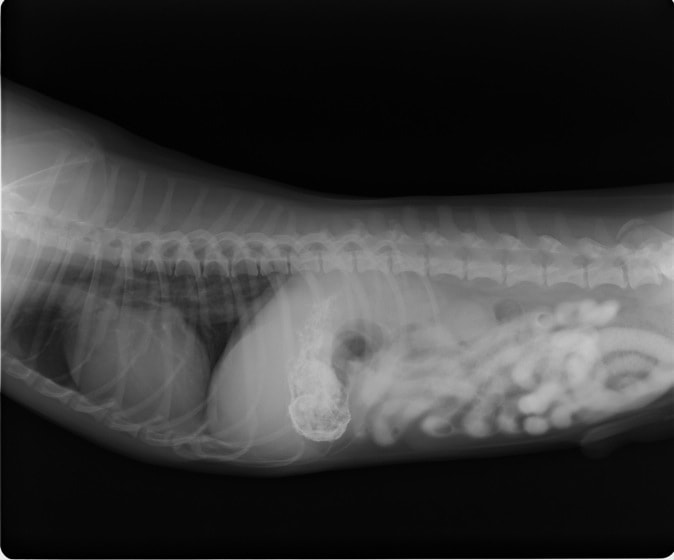

4歳 アメリカンショートヘアー

主訴:3日前から嘔吐が続き、食欲も落ちてきたのこと。

対症療法(症状に対する治療)に反応しないため、精査を実施。

一般血液検査:問題なし

単純レントゲン検査:胃内ガス陰影・腸内ガスが少量認められる。

嘔吐が改善しないため、消化管バリウム造影検査を実施。

以下、

消化管バリウム造影レントゲン

バリウム造影3時間経過するも、胃内からバリウム排泄なく同日内視鏡検査を実施。

内視鏡検査結果:内視鏡下にて、バスケット鉗子を用いて摘出。

症例は、机の上に置いていたピスタチオのお菓子を誤飲していました。その後の経過は良好です。本症例は、内視鏡下にて摘出ができましたが、球状・立体などの大きな異物は、腸の途中で詰まりやすく、内視鏡下での摘出が困難な場合もあります。その際は、開腹下にて腸内の異物を摘出しなくてはなりません。動物たちは、思わぬ物を誤飲することがあります。お留守番時・就寝時は、誤飲をしやすい時間帯ですので注意しましょう。

◎バリウム造影検査とは??

ヒトと同様に特殊な液体を飲み、消化管内のバリウムの流れを経時的に撮影していきます。

胃の粘膜状態、胃から腸への通過障害の有無などを確認することが出来ます。また、単純レントゲンでは写することのできない物もバリウムを飲む事で写し出されることが多くあります。検査をするためには、前日の夜からの絶食が必要になりますが麻酔などは必要ありません。